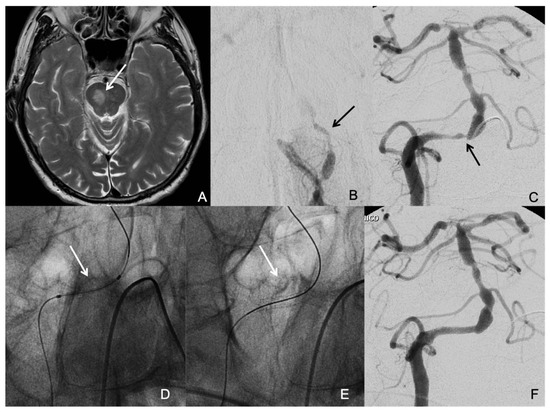

The symptomatic qualifying artery was basilar artery in 15 patients (41.7%), intracranial vertebral artery in 13 patients (36.1%), middle cerebral artery in 3 patients (8.3%), and intracranial internal carotid artery in 5 patients (13.9%). The time from the qualifying event to intervention ranged from 2 to 78 days, with a median time of 17 days. The most likely stroke mechanisms related to ICAD were mixed mechanisms in 47.2% (17/36), hypoperfusion in 27.8% (10/36), and artery-to-artery embolism in 25% (9/36). Neither perforator occlusion nor insitu thrombotic occlusion was present as the sole stroke mechanism in any patient of our study population. Thirteen patients (36.1%) had multiple significant ICAD (Figure 1). Five patients (13.9%) had concomitant significant Extracranial Atherosclerotic Disease (ECAD). Two patients (5.6%) had significant stenosis (≥70%) proximal to the target lesion, i.e., tandem stenosis. Twenty-one patients (58.3%) had tortuous proximal vessels (≥2 acute curves).

Figure 1. A patient who suffered a right medial pontine infarction (arrow in (A)) and had several drop attacks due to a low flow situation based on a total occlusion of the left vertebral artery (arrow in (B)) and severe stenosis of the right vertebral artery at the vertebra-basilar junction (arrow in (C)). The aim of the treatment was to correct vertebrobasilar hypoperfusion. The decision was to revascularize the right vertebral artery and to leave the occluded left vertebral artery without intervention. An undersized coronary balloon-expandable stent was placed in the right vertebral artery at the site of the stenosis (arrows in (D,E)) with good resolution of the stenosis (F).